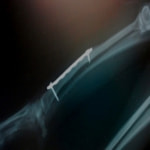

症例:交通事故による椎体脱臼

柴犬:9歳、避妊雌

交通事故直後、胸腰部に激しい疼痛、両後肢に完全麻痺を認め、シェフシェリントン徴候を呈していました。レントゲン検査において、第11-12胸椎間の脱臼が認められました。

脊髄の減圧、脊柱管の再構築・安定化を目的に、片側椎弓切除術およびMatrixMANDIBLE Plateによる椎体固定を実施しました。

隣接椎体を架橋するようにプレートを設置しました。

術後レントゲン写真